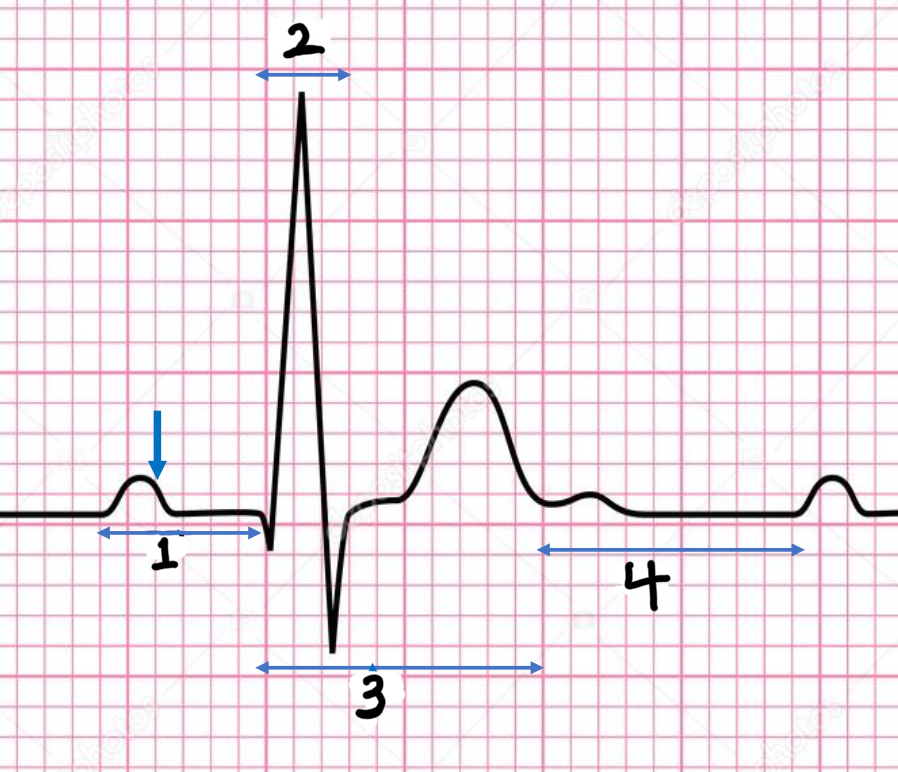

P wave

atrial depolarization

Precedes atrial contraction

QRS complex

ventricular depolarization

Precedes ventricular contraction

T wave

ventricular repolarization

PR interval

Name #1

QRS interval

Name #2

QT interval

Name #3

TP interval

Name #4

PR interval

time from beginning of the P wave to the beginning of the QRS complex

QRS interval

Time from beginning of the QRS complex to the end of the QRS complex

QT interval

Time from beginning of QRS complex to the end of the T wave

TP interval

Time from end of T wave to the beginning of P wave